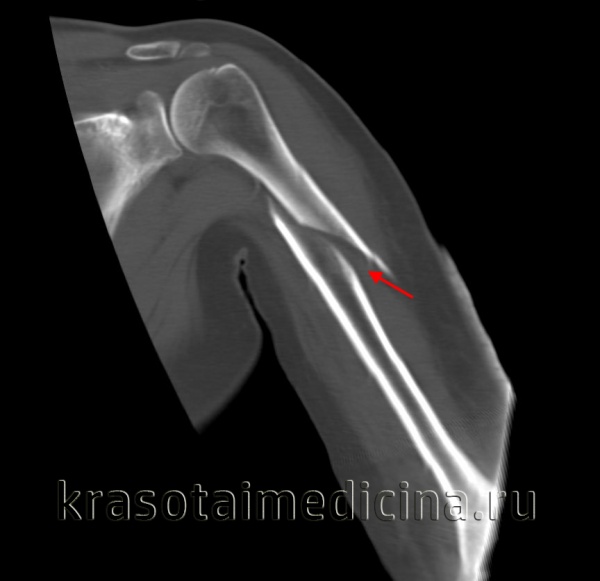

Наиболее точная информация о характере перелома может быть получена с помощью компьютерной томографии с пространственной реконструкцией.

Компьютернаятомограмма: перелом тела лопатки.